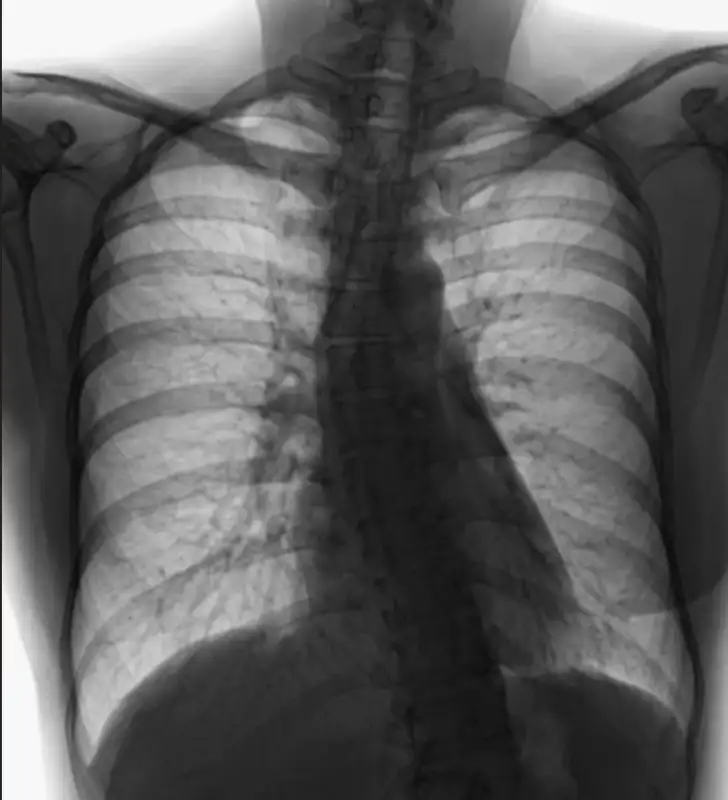

Skoliosis adalah kondisi ketika tulang belakang melengkung ke samping membentuk huruf S atau C. Banyak orang baru menyadarinya saat bahu terlihat tidak sejajar, pinggang miring, atau sering pegal di punggung. Padahal, dengan penanganan yang tepat, penderita skoliosis tetap bisa hidup aktif, nyaman, dan percaya diri.

Skoliosis bukan sekadar “postur buruk”. Ini adalah kelainan struktur tulang belakang yang bisa bertambah berat seiring dengan pertumbuhan, terutama pada anak dan remaja.

Diagnosis pasti ditegakkan dengan rontgen untuk mengukur derajat kelengkungan.